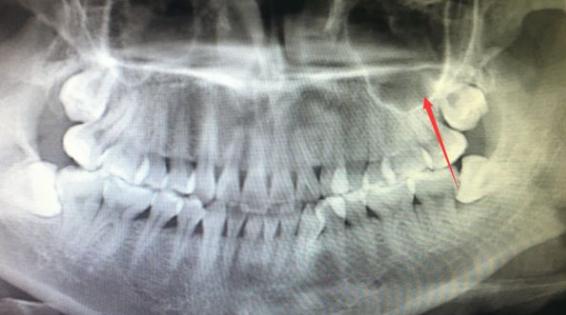

问:智齿歪了,但是一点都不疼,是不是就不用拔了?

一定要拔!长歪的智齿也可能影响到隔壁的牙齿,当然如果你想日后多拔一颗,倒确实可以留着。